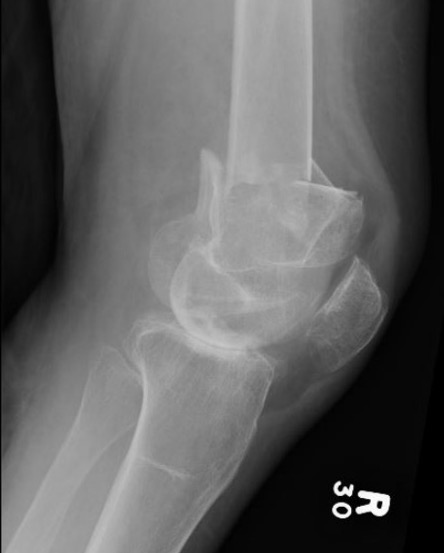

AO Type B1 & B2: Partial articular

![]()

Definition

Medial or lateral sagittal split

Technique

ORIF

- medial or lateral approach based on fracture location

- reduce articular split and fix with screws

- medial or lateral buttress plate

Lateral split fracture distal femur